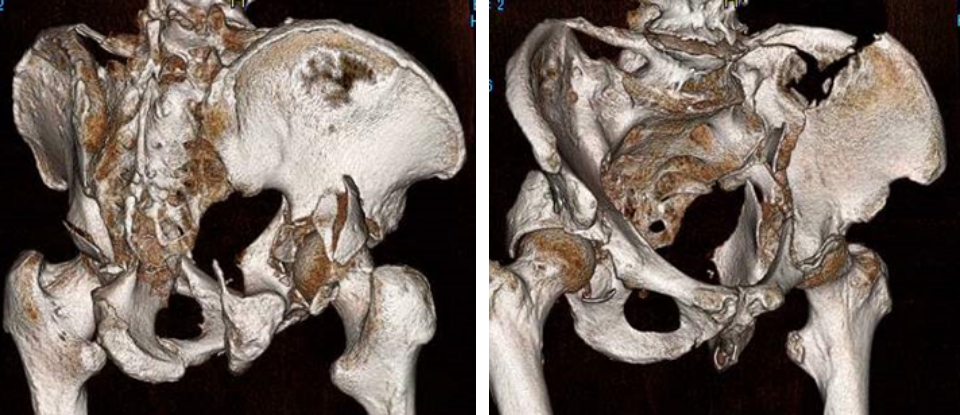

側寛骨臼骨折3D-CT

さらに当科の最大の特徴は整形外傷手術において最も難易度の高いうちの一つとされる骨盤・寛骨臼骨折治療を得意としているところであります。

現在年間50~60件の骨盤・寛骨臼骨折手術を当科で行っており、これは東海地区でもトップクラスであり、近隣の病院からも多くの手術目的の紹介をいただいております。

骨盤・寛骨臼骨折は受傷時に大量出血にて生命を脅かし得る損傷ですがこれに対しても迅速な血管塞栓術の対応が可能となっております。また近年こうした骨盤・寛骨臼骨折の患者様も高齢症例が増加しており内科的合併症が多い場合もございますがこれに対しても内科系救急医と協力し患者様に最善の治療を提供させていただいております。